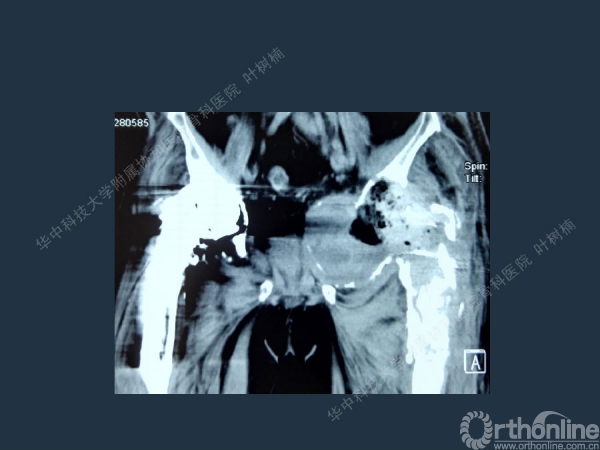

股骨侧翻修

髋臼缺损的处理